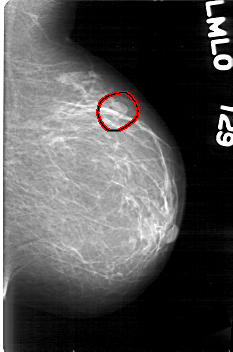

D_4045_1.LEFT_MLO

LEFT_MLO LINES 5266 PIXELS_PER_LINE 3481 BITS_PER_PIXEL 12 RESOLUTION 43.5 OVERLAY

FILE: D_4045_1.LEFT_MLO.OVERLAY

TOTAL_ABNORMALITIES 1

ABNORMALITY 1

LESION_TYPE MASS SHAPE LOBULATED MARGINS OBSCURED

ASSESSMENT 0

SUBTLETY 3

PATHOLOGY BENIGN

TOTAL_OUTLINES 1

BOUNDARY